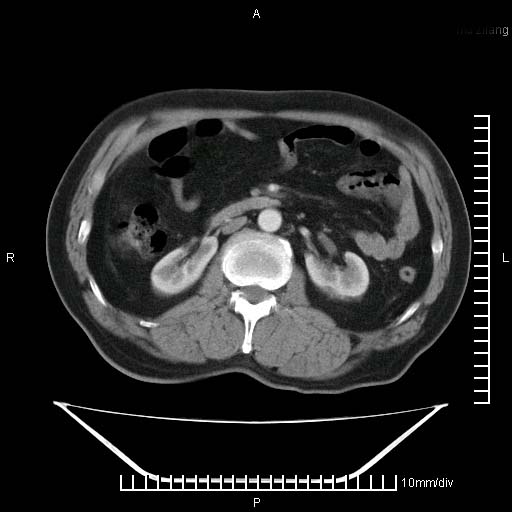

标题: CT25082:肝脏增强:男性,70岁 [打印本页]

标题: CT25082:肝脏增强:男性,70岁

患者以心脏疾病收住院,腹部无明显症状,b超查肝脏有占位。

增强效果不理想。考虑转移,胆囊壁明显增厚,不排除胆囊癌肝转移。

病灶无强化,考虑囊肿。

牛眼征,中心坏死无强化,外缘强化,最外缘又见低密度,考虑转移,与脓肿鉴别

肝内多发转移瘤,右下肺炎症并少量胸水。胃壁增厚建议胃镜,胰尾部“病变”为肠管。

1)肝脏多发性转移瘤(不排除胰尾癌转移所致可能)。2)腹水。3)右侧少量胸腔积液。

ct25082 结果:转移瘤

外院mr结果:胰尾恶性占位。